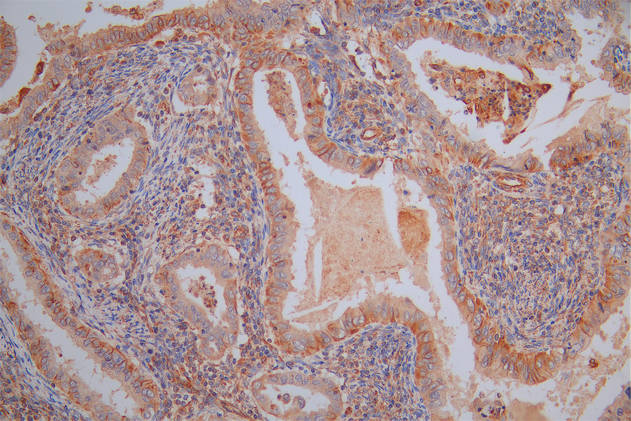

圖片:

應(yīng)用范圍:ELISA, IHC

Application Recommended Dilution IHC 1:20-1:200 -